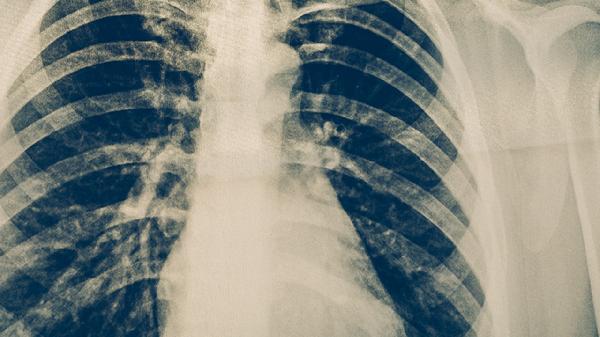

胸部X線可顯示肺結(jié)核特征性病變,如上葉尖后段或下葉背段的浸潤(rùn)影、空洞形成等。典型影像學(xué)表現(xiàn)結(jié)合臨床癥狀可初步診斷,但需注意與其他肺部疾病鑒別。對(duì)于疑似病例可能需要進(jìn)行胸部CT檢查以獲取更清晰的影像細(xì)節(jié)。影像學(xué)改變可能滯后于臨床癥狀。